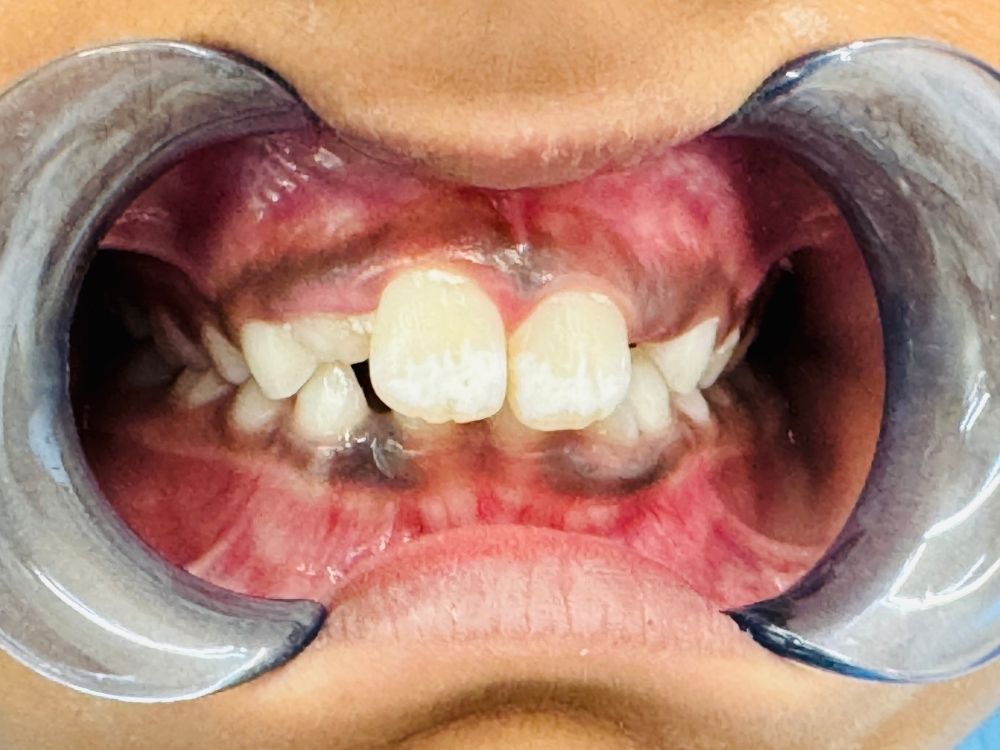

Regular cleanings help keep your child’s smile bright and cavity-free. If a cavity does occur, our gentle fillings restore the tooth’s strength and appearance. We also apply sealants to protect the grooves of your child’s molars — preventing decay before it starts.

As your child’s mouth grows, our team monitors their dental development closely. If a baby tooth is lost too early, a space maintainer helps preserve room for the permanent tooth to erupt correctly. In cases where a tooth needs extra protection, we may recommend stainless steel crowns to restore its function and durability — keeping your child’s smile healthy and strong.